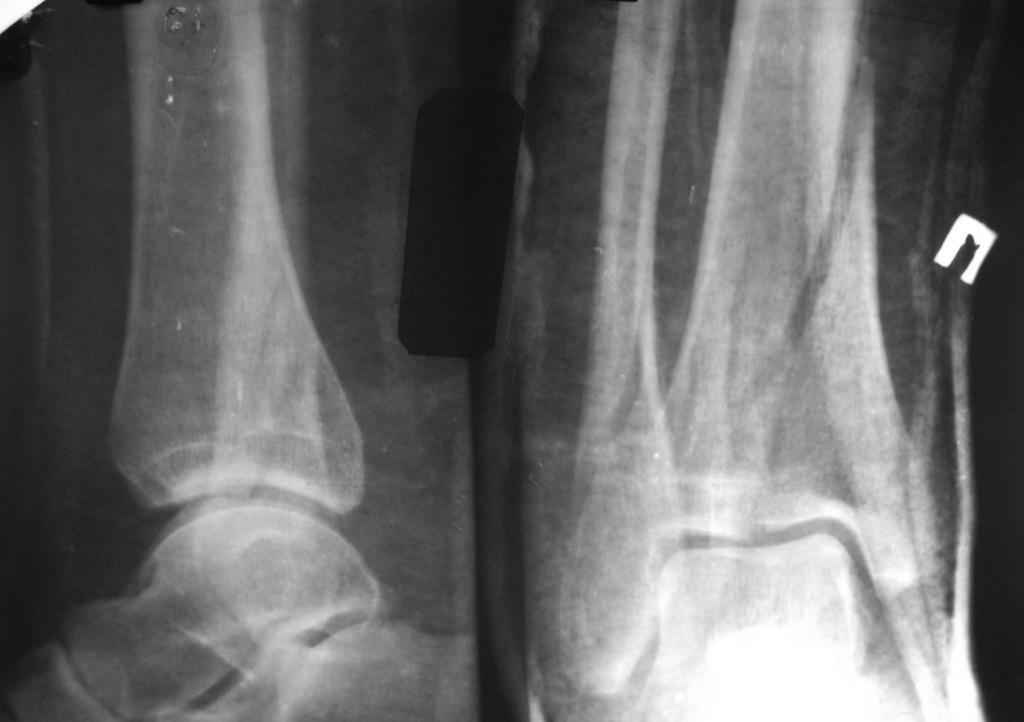

помогите определиться с тактикой лечения даного перелома пилона

Больной, 46 лет. Травма 27.08.08. При поступлении, в травмпункте была проведена блокада места перелома, иммобилизация гипсовой повязкой. Единого мнения по поводу дальнейшего лечения пока нет. Просьба высловиться по поводу возможностей лечения даного перелома, вообще возможности оперативного лечения. Спасибо за ответы.

прошу прощения за то, что забыл приложить снимки

открытая репозиция и фиксация

- малоберцовая - 3.5 мм 1\3 трубчатая пластина.

- большеберцовая - масса вариантов, начиная с множественных шурупов без пластины и заканчивая locking plate для дистальной тибии